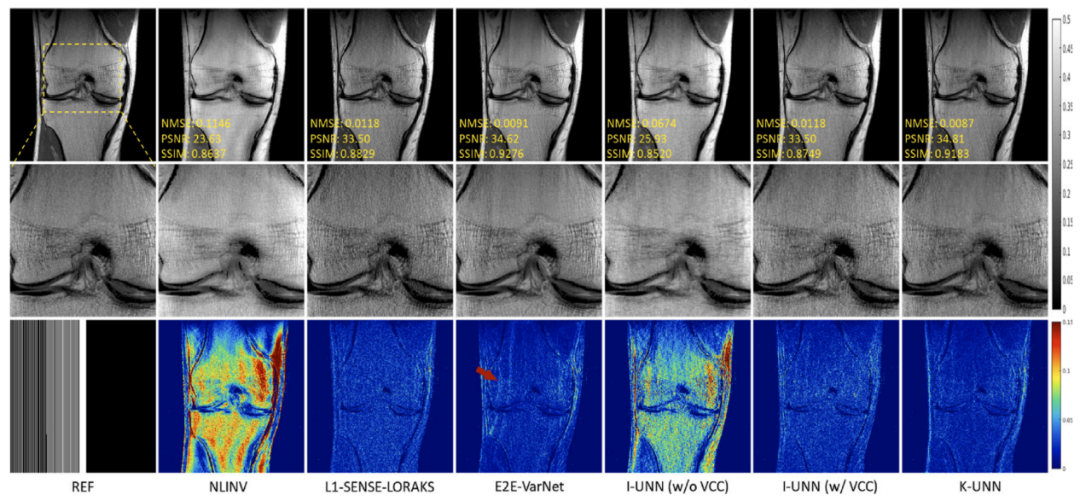

磁共振利用多通道线圈接收人体生理信号,多线圈的数据间具有很强的相关性。团队针对磁共振成像中全采数据难以取得的巨大挑战,提出利用线圈间数据相关性这一物理先验,来构建磁共振物理驱动的无监督深度神经网络成像模型,并分析了网络的误差上界,为成像可靠性给予保障。实验结果(图1)表明,该方法无需训练数据就能够重建出高质量图像,且效果与需要训练数据方法类似。研究成果发表在医学成像领域著名期刊Medical Image Analysis。

图1. 5倍加速重建结果